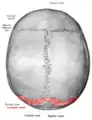

Lambdoid suture (labeled at bottom right)

The lambdoid suture (or lambdoidal suture) is a dense, fibrous connective tissue joint on the posterior aspect of the skull that connects the parietal bones with the occipital bone. It is continuous with the occipitomastoid suture.

The lambdoid suture is between the paired parietal bones and the occipital bone of the skull. It runs from the asterion on each side.